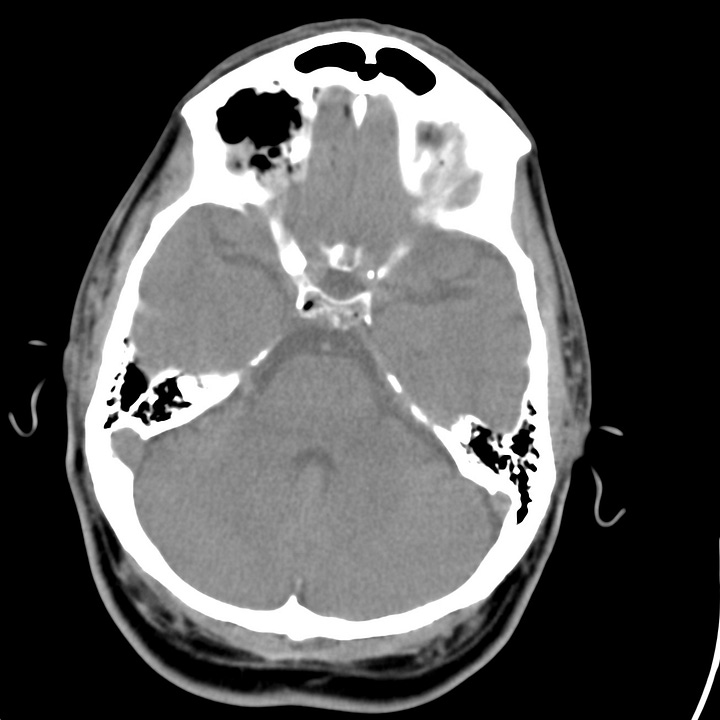

Tension pneumocephalus due to temporal bone fracture. Bifrontal subdural air collections with mild compression of the frontal parenchyma. Opacified left mastoid air cells are consistent with an acute tem- poral bone fracture. Air in the cisterns and left sylvian fissure indicate arachnoid injury.